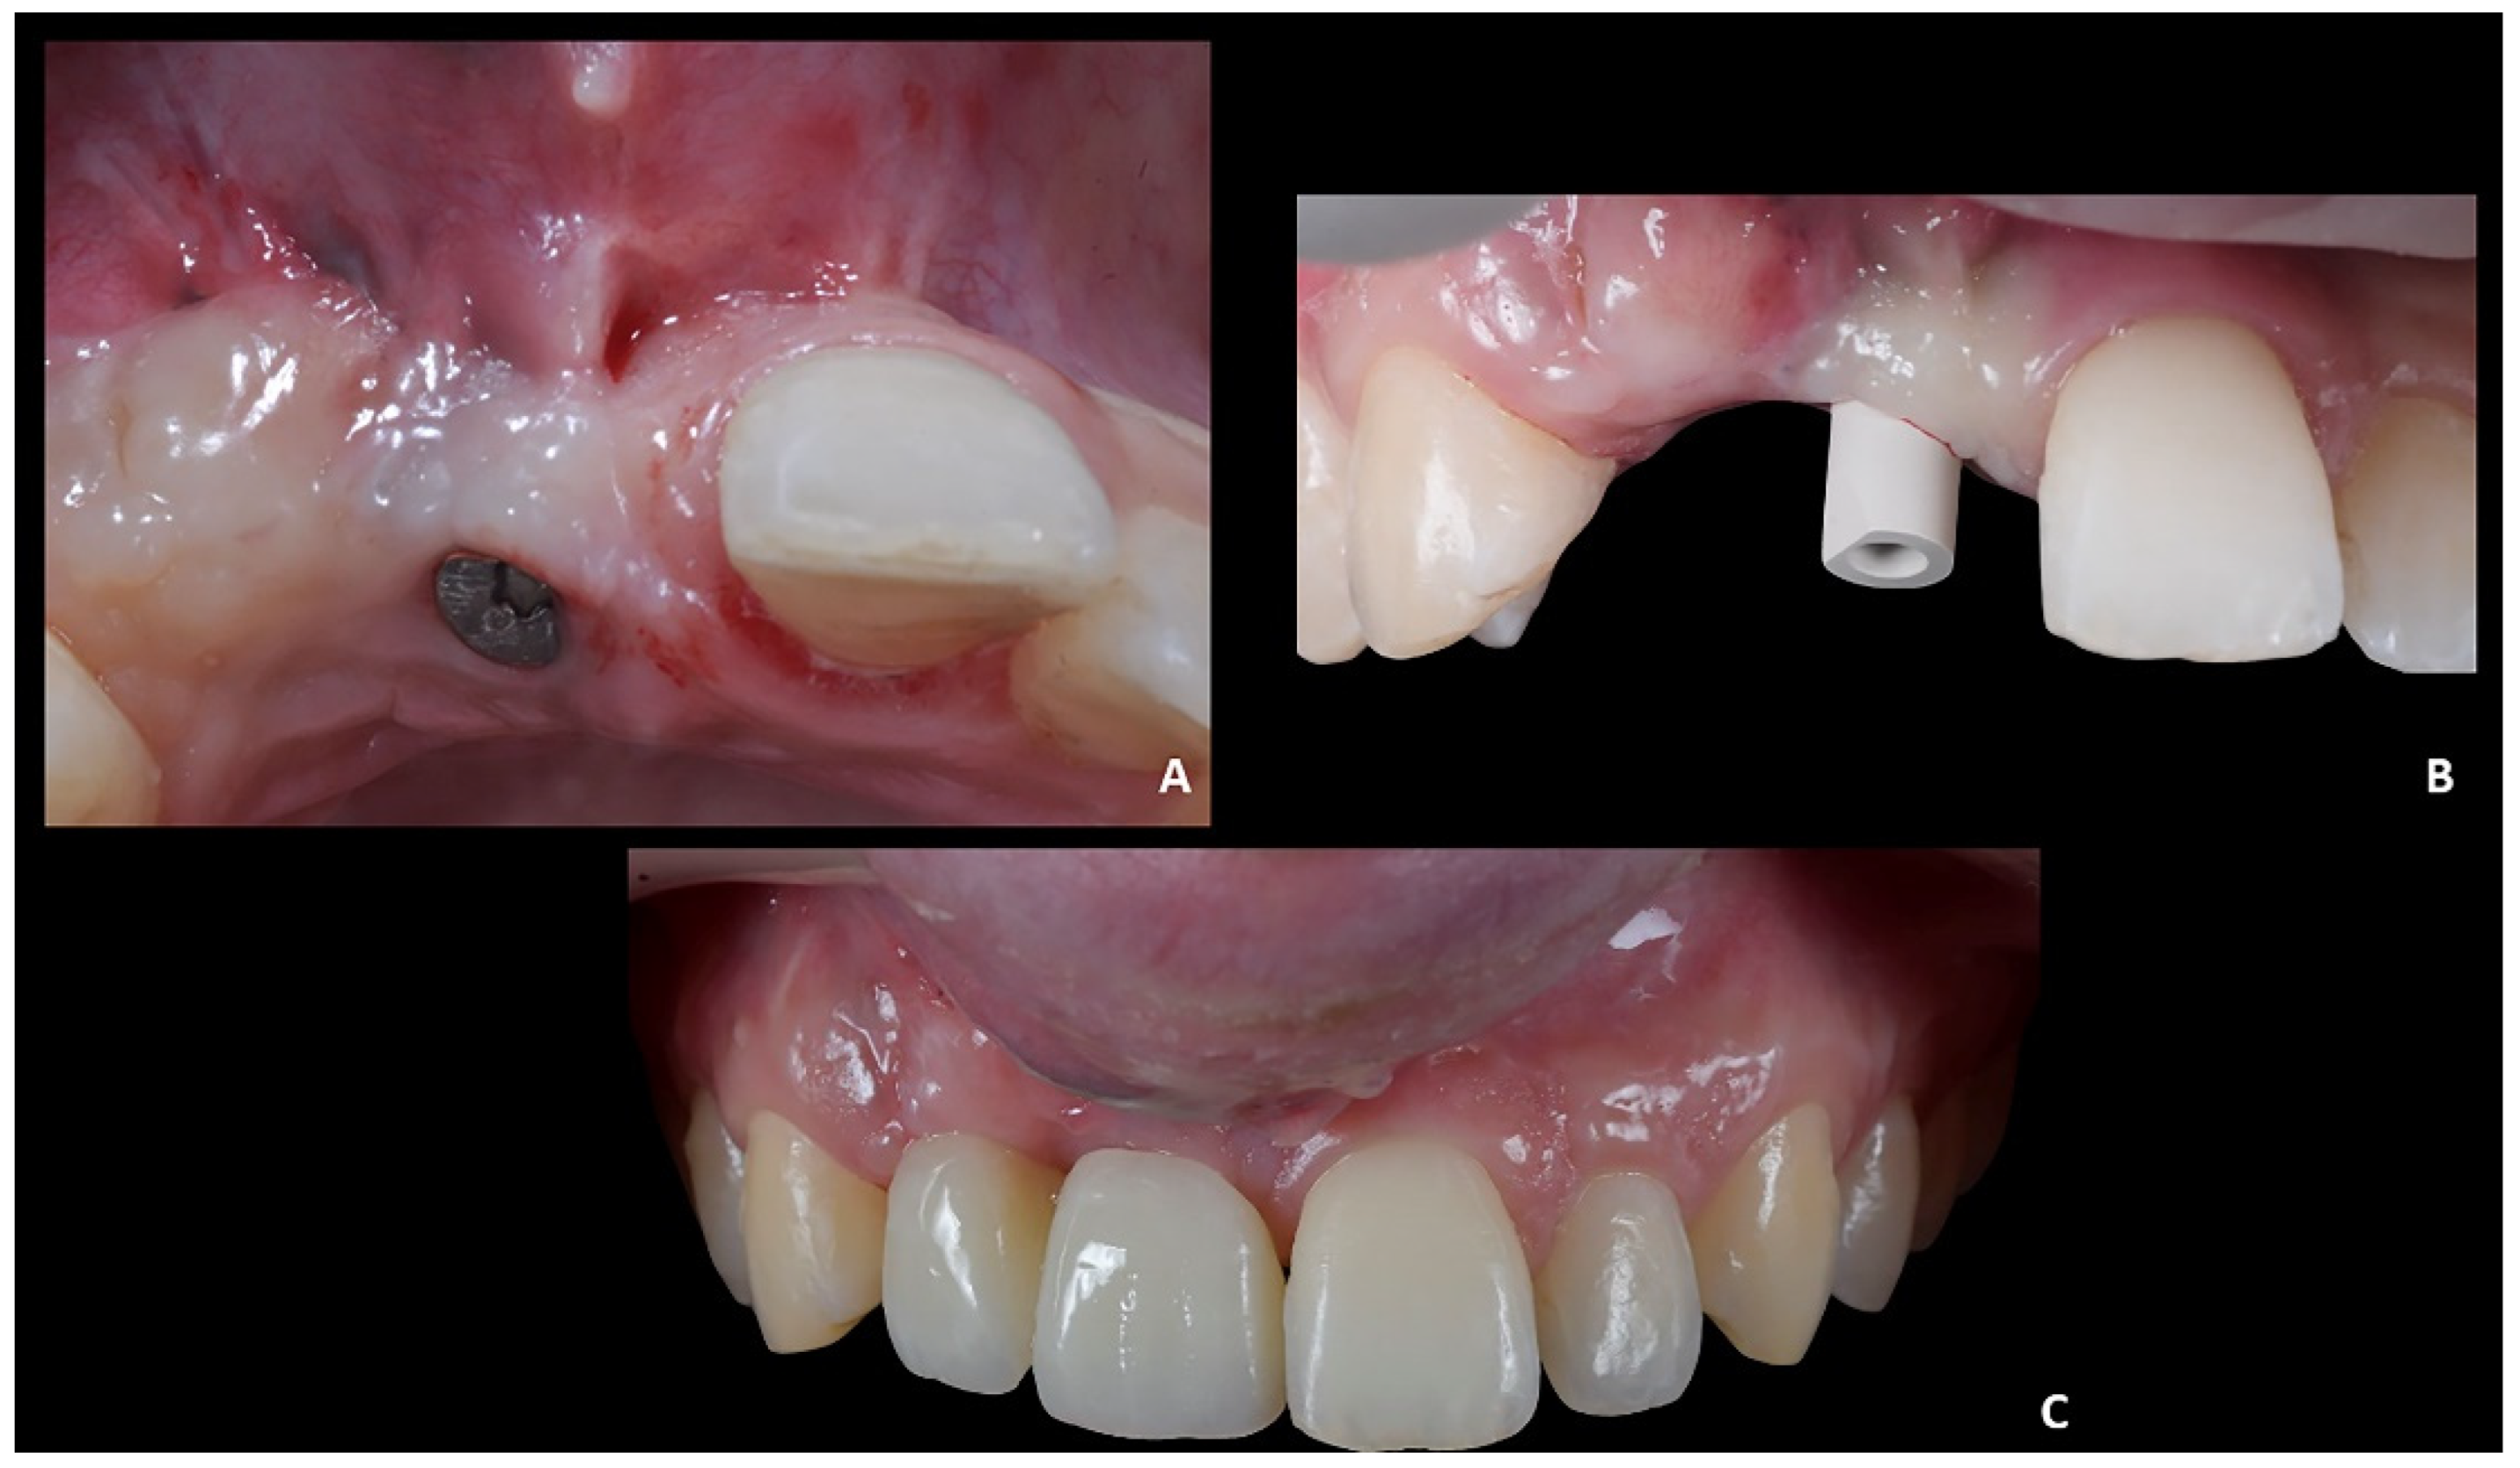

• Prosthetically guided implant planning. After removing the provisional prosthesis, an intra-oral scan was recorded, and the lab technician was asked to produce a virtual wax-up of the ideal position of the teeth. A Cone-Beam Computed Tomography (CBCT) was performed, and the 3D rendered model of the maxilla was registered with the intra-oral scan using the implant planning software Co-Diagnostix (Straumann, Montreal, Canada) (Figure 9). The software was used to plan the implant’s ideal position and design a surgery guide. Figure 10 shows the clinical procedure of the guided implant surgery. Once the osseointegration occurred, an intra-oral scan was performed to register the position of the implant and the surrounding soft tissues with the healing abutment in place (Figure 11A,B).

Positioning of the provisional prosthesis (11 with cantilever 1.2). The scan file was sent to the lab technician, which was asked to design a fixed temporary prosthesis in polymethyl methacrylate (PMMA), screwed onto the implant, and with the following instructions: (1) designing the 1.1 and 1.2 with the same size of contralateral teeth, and (2) maintaining the ideal overjet and overbite ratio compared to opposite arch (Figure 11C).

Figure 11. Case 2. (A) Healing abutment; (B) intra-oral scan with scan-body to detect the axial orientation of the implant; (C) prosthetic restoration.